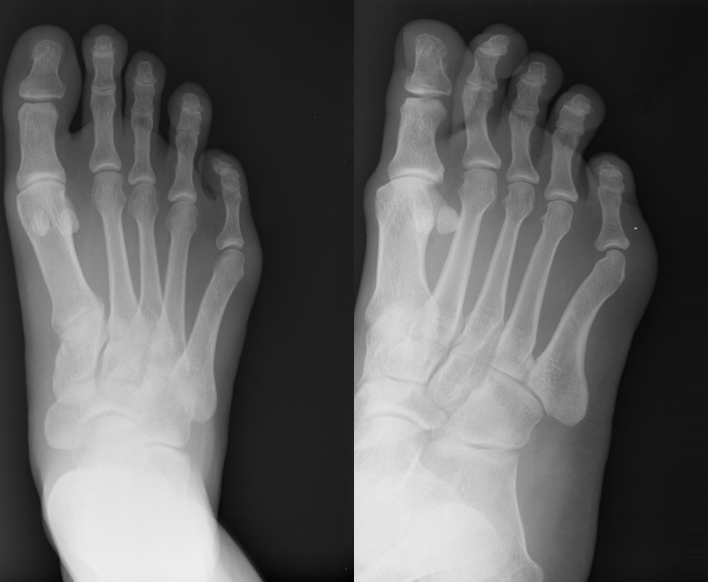

Pre op oblique view - hammer toes #2 and 3

Post op AP view hammer toes 2-5